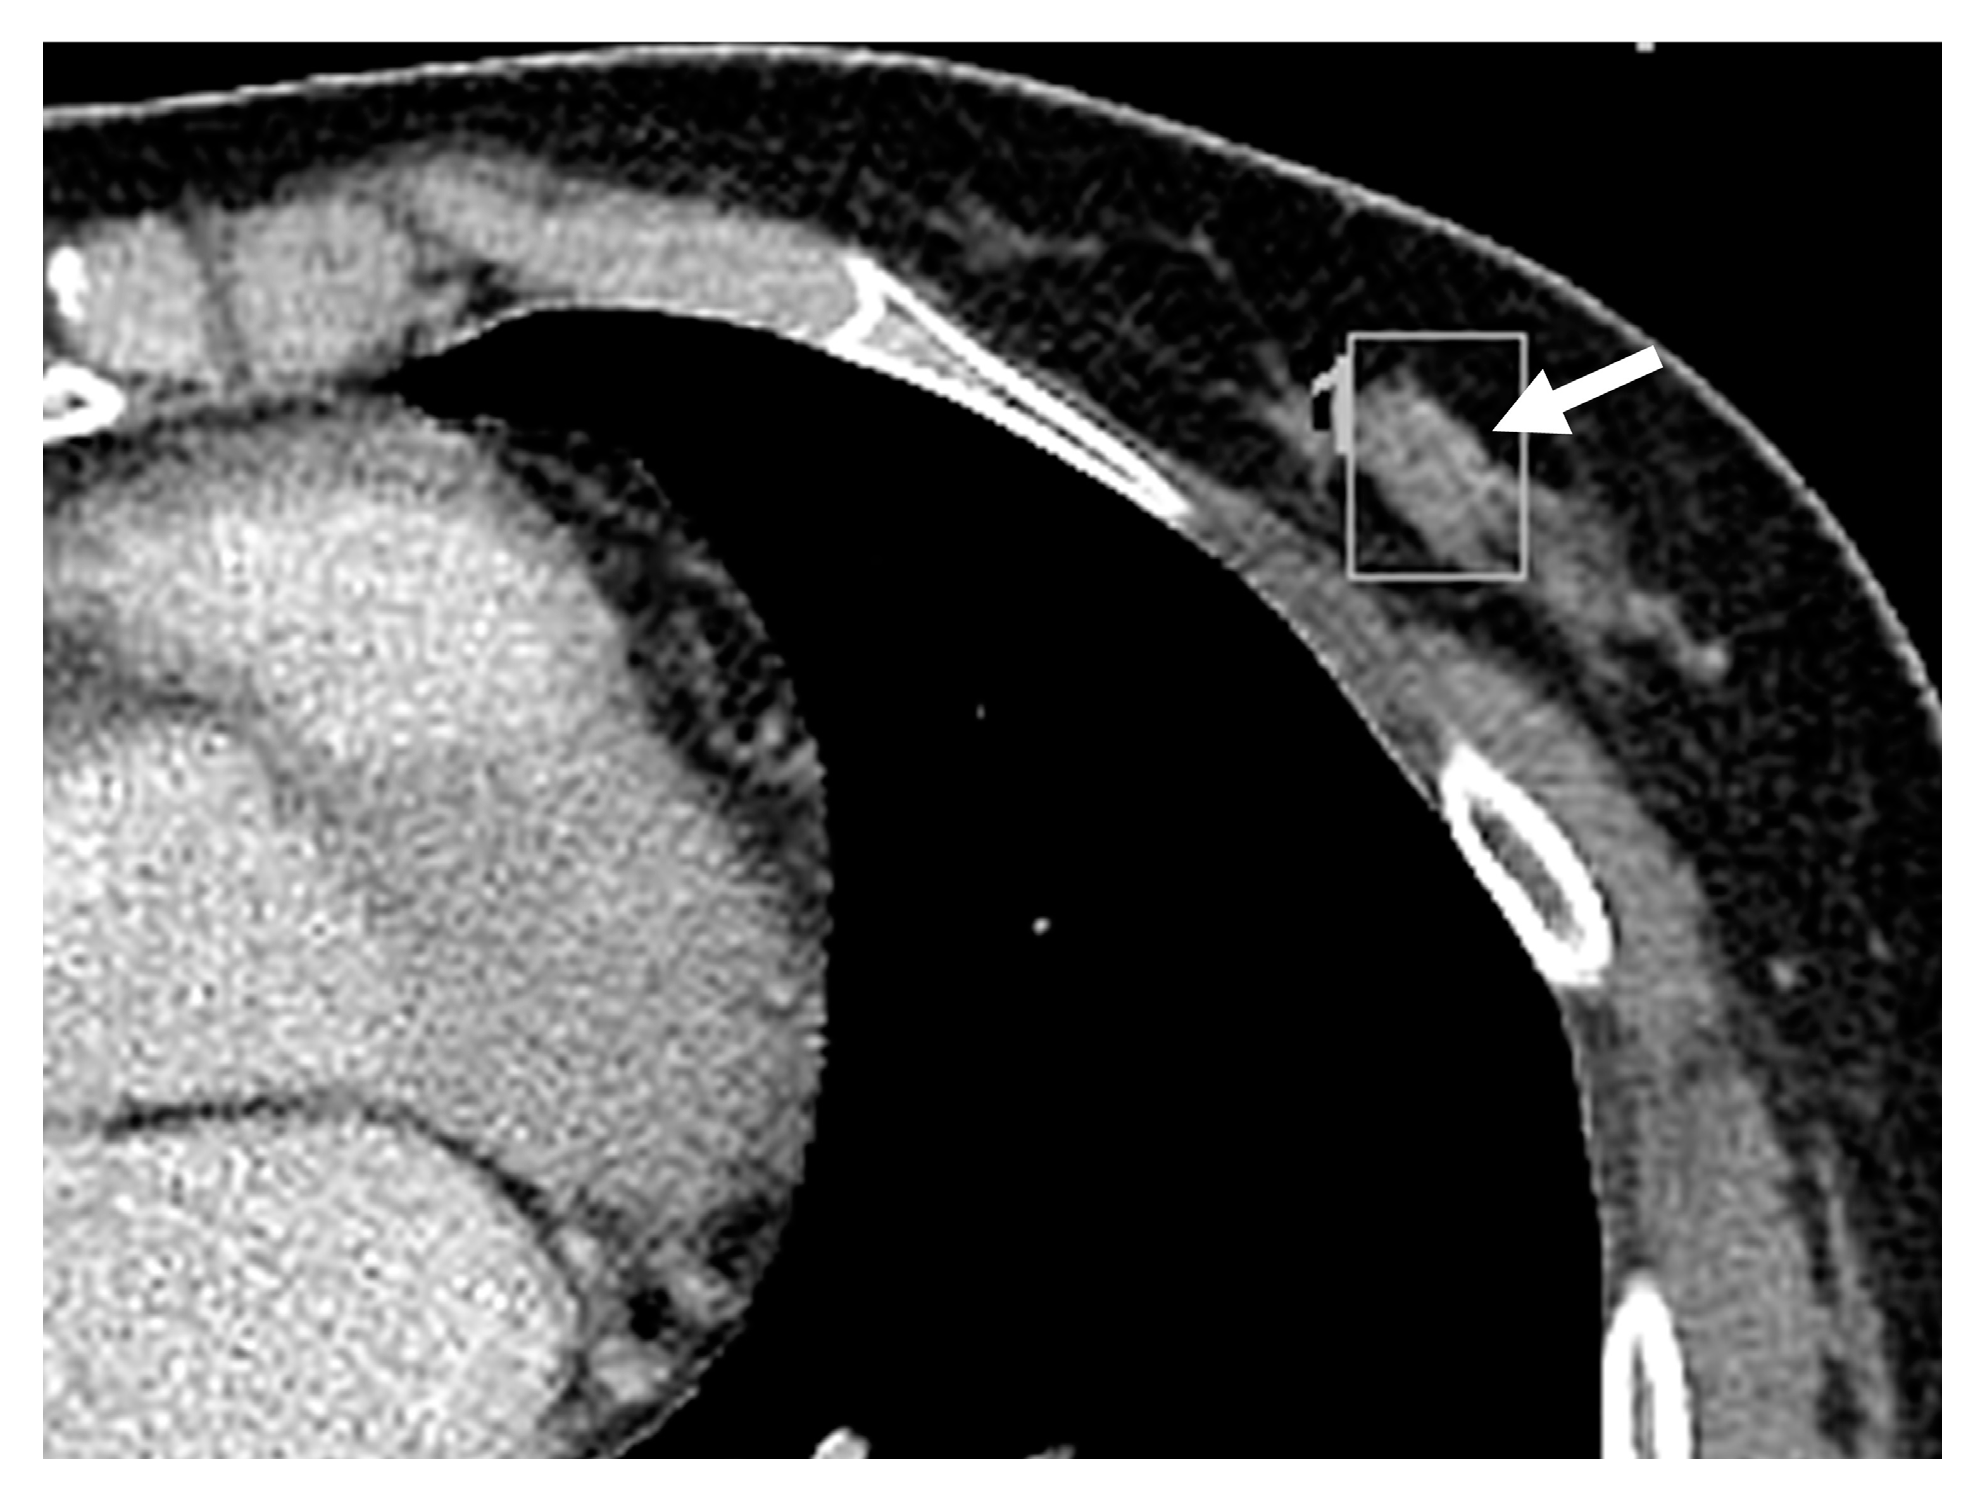

3.2. Imaging Features of Missed and Detected Breast Cancers

3.3. Imaging Features Associated with Missed Breast Lesions Group